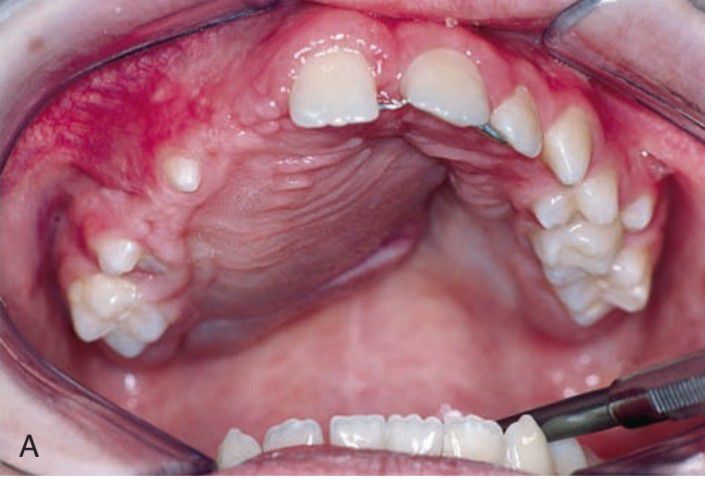

Central giant cell granuloma

CGCG occurs almost exclusively in the maxilla and mandible, although isolated cases in facial bones and small bones of the hands and feet have been reported. Lesions are seen more commonly in the mandible than in the maxilla